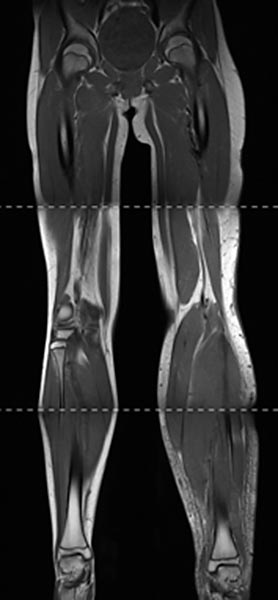

Composite T1-weighted coronal MRI from the pelvis to the feet. Not only the leg length discrepancy (osseous hyperplasia) is clearly visible, but also the significantly larger musculature on the left side and the enlarged adipose tissue. The hyperplasia of the extremity affects all tissues in Parkes-Weber syndrome.